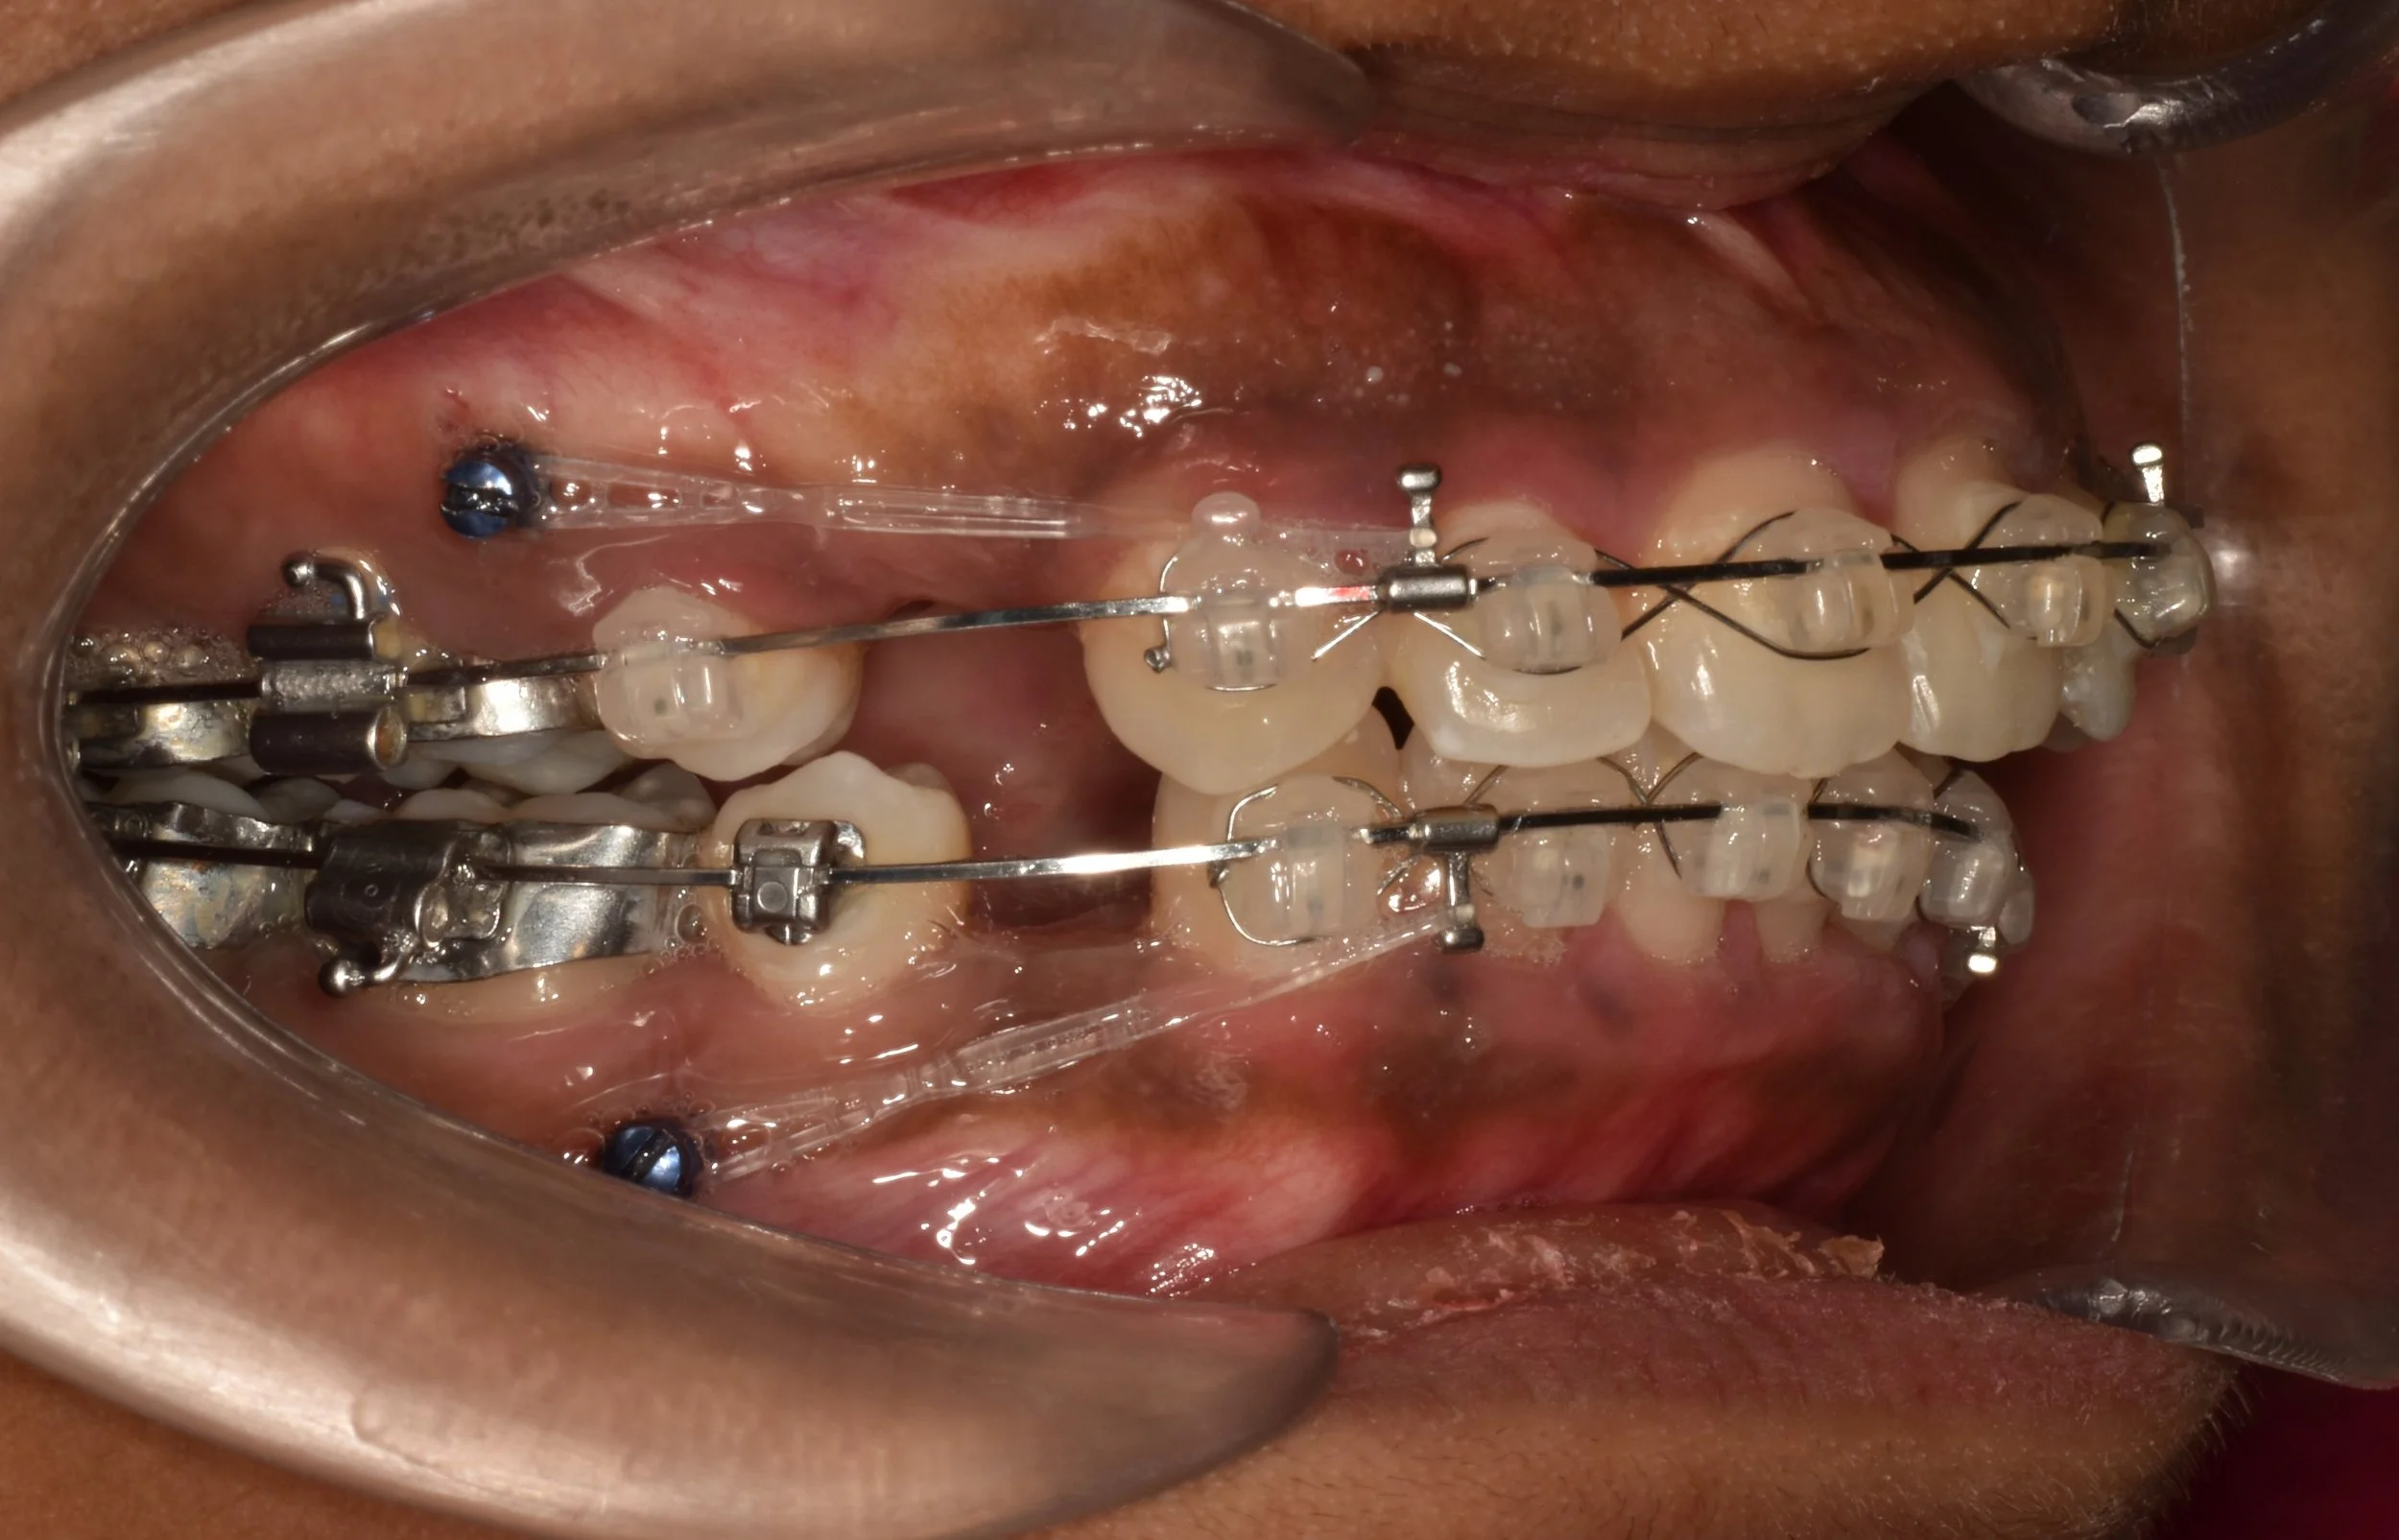

Extra-radicular implants